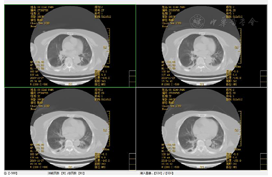

2019年8月3日急诊头颅CT提示:右侧脑出血,伴蛛血(图1)。2019年11月27胸日部CT提示:肺部感染,部分实变(图2、图3)。呼吸功能评估:胸廓活动度明显下降,呼吸肌肌力和耐力下降,无自主咳嗽。绿染实验提示患者有误吸,无食道反流情况。吞咽功能评估:存在误吸,咳嗽力量欠佳,口腔运送能力差,吞咽启动明显延迟,咽缩肌无力,下颌运动受限。

4.治疗中期及拔管前功能评估:未吸氧,血氧饱和度正常范围,生命体征平稳。主动张口幅度1.5 cm,被动张口幅度2.5 cm,自主咳嗽能力正常、自主清嗓较稍减弱,咽反射正常,吞咽启动减慢,喉上抬范围1.0 cm,简易吞咽诱发试验正常。气切管固定稳妥,未见异常分泌物。经气切口通气,呼吸平稳;膈肌移动度及呼吸肌肌力和耐力正常。Brunnstrom运动功能评定:左上肢3期、左手3期、左下肢4期。左侧肢体浅感觉较对侧减退,左肘及左膝关节平面以下感觉减弱。颈部被动活动无明显受限。站立平衡1级及坐位平衡2级。完善吞咽造影检查:可进食1、2、3号食物,吞咽造影提示患者吞咽启动减慢,吞咽耐力部分下降(视频2)。拔管前辅助检查评估:(1)完善颈部CT未见颈部无软组织肿胀及呼吸道受压;(2)电子鼻咽喉镜未见气道狭窄,声门开放可(视频3);(3)未吸氧情况下血气分析未见明显异常,肺功能大致正常;(4)肺部CT(图4、图5)提示感染基本控制,炎症明显吸收,血感染指标正常;(5)连续堵管训练24 h,患者血氧饱和度及血气分析正常。